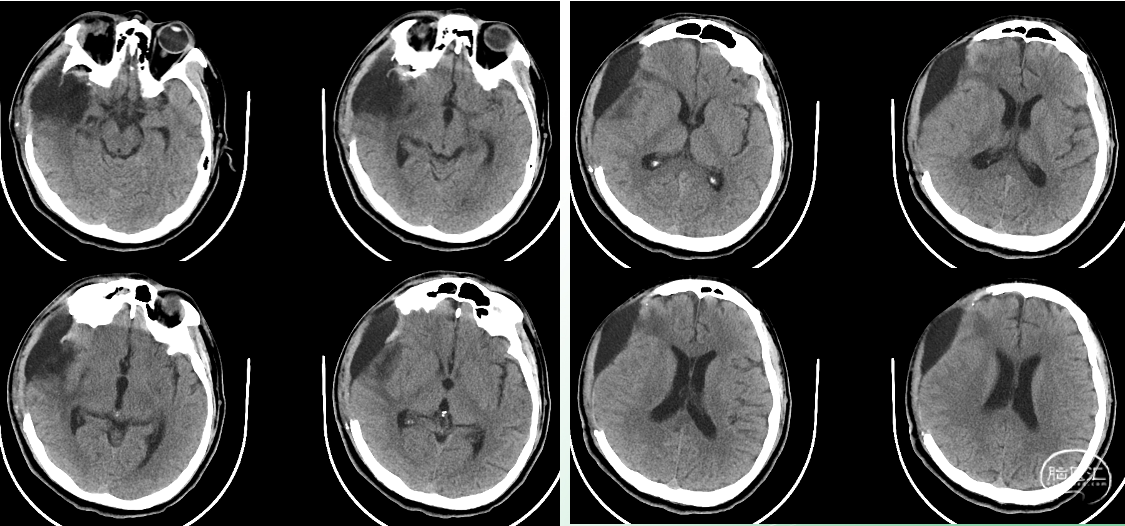

入院时影像

急诊颅脑CT+三维重建:

颅脑锐器损伤并异物存留,异物由右侧眼眶刺入颅内;右侧额颞叶挫裂伤并血肿形成;蛛网膜下腔出血;脑室系统较多积血;右侧额颞顶部少量硬膜下积血